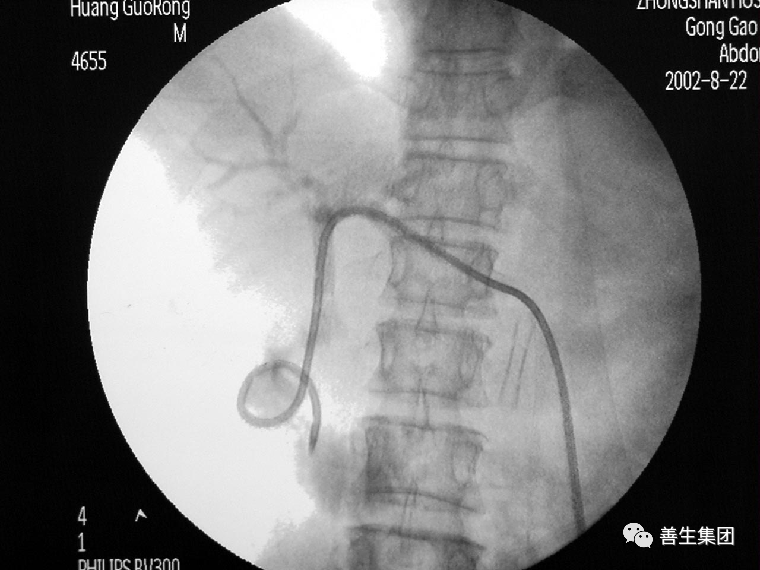

右肝MT,伴梗阻性黄疸。先穿刺右侧胆管,发觉左侧胆管更顺,改穿左侧。

导管、导丝通过狭窄段

金属内支架+局部狭窄扩张后

金属内支架+引流管